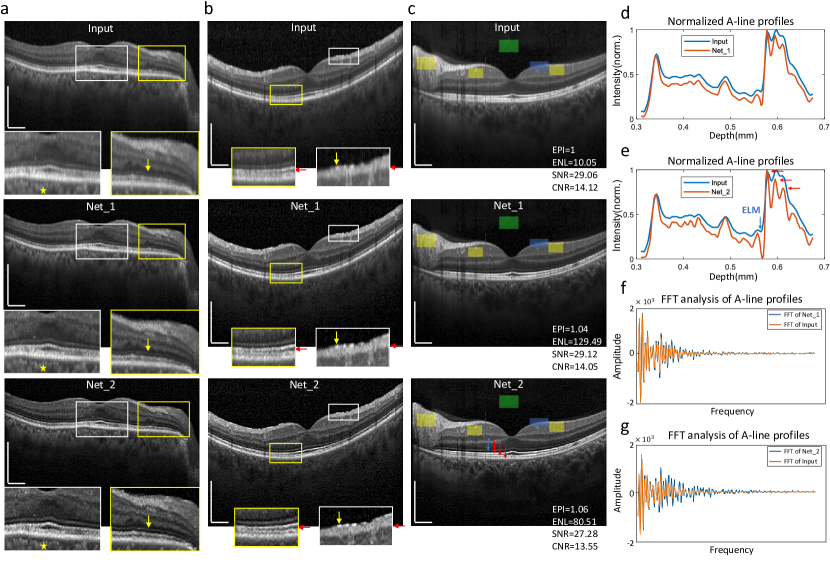

Fig. 4: Recurrent inference and resolution quantification. a-c, Input: retina OCT images from dataset 1 (Spectralist in Supplementary Table 1), Net_1 = modelr𝑚𝑜𝑑𝑒subscript𝑙𝑟model_{r}(Input), Net_2 = modelr𝑚𝑜𝑑𝑒subscript𝑙𝑟model_{r}(0.3 Input+0.7 Net_1), insertions are 2 times zoom-in figures, green patches in c are regions selected as background, blue patches are regions selected for EPI calculation and yellow patches are selected for CNR calculation. d-e, normalized intensity of a cropped rang of A-lines labeled by red dashed lines in c. f-g, FFT analysis of the whole A-lines at the same horizontal locations as in d and e. Scale bar: 0.5 mm.

Fig. 4 illustrates the gradual refinement of input images through the utilization of a recurrent inference strategy. The training process follows the same procedure as models𝑚𝑜𝑑𝑒subscript𝑙𝑠model_{s}, except for the use of a narrower PSF (Supplementary Fig. 2c). The trained model is named as modelr𝑚𝑜𝑑𝑒subscript𝑙𝑟model_{r}. The zoom-in images in Fig. 4 clearly illustrate that Net_1 images exhibit a higher resolution compared to their inputs, while Net_2 images achieve an even higher resolution than Net_1. In Fig.  4a, yellow arrows within yellow boxes indicate the external limiting membrane (ELM), which is resolved with the highest clarity in Net_2. Net_1 also shows improved visibility compared to the input. For the choroid, denoted by yellow stars in white boxes, Net_2 achieves the highest level of clarity, and Net_1 also shows significant improvement compared to the input. In Fig. 4b, within the zoomed-in white boxes, a small hyper-reflective foci indicated by a yellow arrow appears blurry in the input image but becomes much clearer in Net_1. In Net_2, not only is the small structure easily isolated from the nerve fiber layer below, but the boundaries of other retinal layers, indicated by red arrows, are also much clearer and sharper. These observations collectively demonstrate the superior resolution achieved by Net_2.

To quantitatively evaluate the resolution enhancement capability of our model, we calculate and provide EPI, ENL, SNR, and CNR values in the bottom right corners of the images in Fig.  4c. Upon analyzing these values, it becomes evident that Net_1 achieves the highest ENL and SNR, whereas Net_2 demonstrates the superior EPI. Taking into account both the detailed reconstruction performance and the evaluation metrics, we conclude that the recurrence technique facilitates continuous resolution improvement but also amplifies the noise level. Therefore, a balance must be struck between resolution and SNR. Figs. 4d-e depict the averaged A-line intensities of five adjacent A-lines of the input and ‘Net’ images in Fig. 4c. By examining the intensity distribution, we are able to evaluate resolution by identifying and quantifying layer boundaries. The ELM and the three layers below it (red arrows in Figs.  4c and 4e) are most clearly discernible in Net_2, once again demonstrating the effectiveness of our method. Figs. 4f-g present the results of Fourier transform analysis. Net_1 exhibits more high frequencies associated with small structures and details compared to the input, while Net_2 contains even more high frequencies related not only to details but also to additional noise.